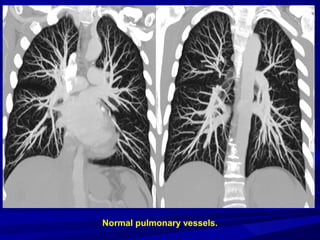

A diagnosis of PE is established

on the basis of individual

transverse sections, although,

extensive or

isolated PE,

as well as normal pulmonary

vasculature can be visualized by

means of 3D reconstructions.

Normal pulmonary vessels.